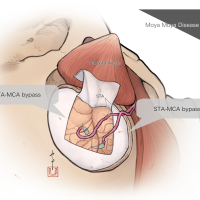

監修:谷川 緑野 / 札幌禎心会病院脳卒中センター

術後イラストシリーズ